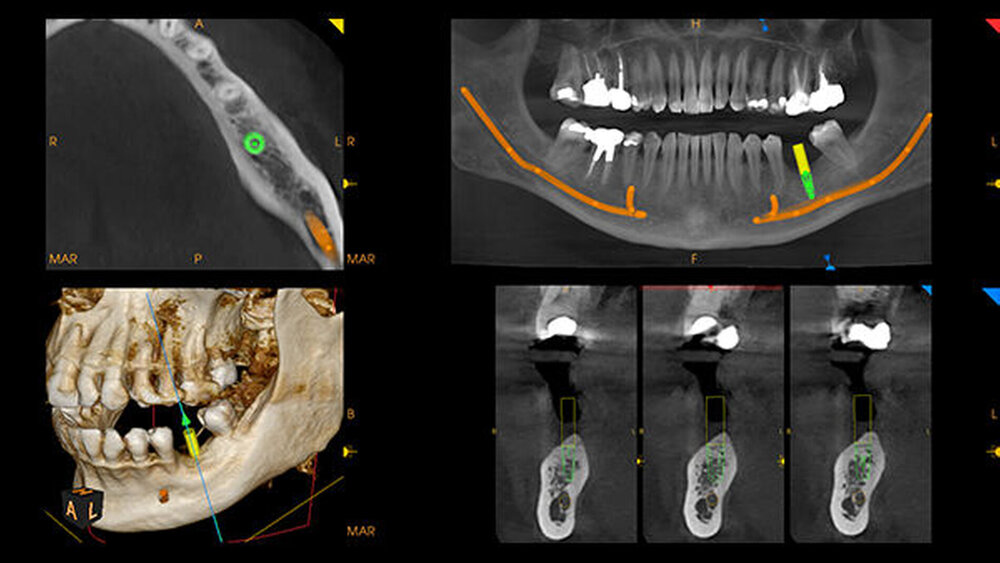

Mithilfe der einzigartigen CS MAR-Technologie mit Live-Vergleichs-Funktion bietet Carestream Dental zusätzlich ein optional auswählbares 3D-Bildgebungsfeature an: Die automatische Metall-Artefakt-Reduzierung sorgt dafür, dass Metallobjekte im Mundraum klarer dargestellt werden. Ein Echtzeit-Vergleich mit einer Aufnahme ohne CS MAR bietet dem Behandler stets den besten Blick auf die Behandlungssituation. Angesichts dieser innovativen Produktfeatures ist der CS 8200 3D die Lösung für nahezu alle täglichen Bildgebungsanwendungen.